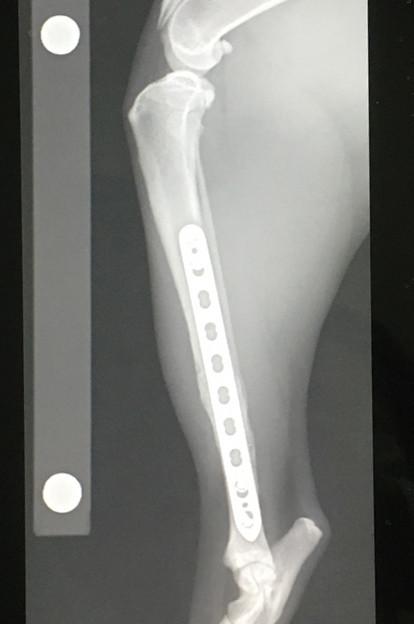

2021年6月、骨折してから約10ヶ月&プレート抜去手術(1回目)から3ヶ月経過しての検診に行ってきました。

レントゲン撮って「順調です」って言われてお会計してくるルーチン。

もう飼い主も先生も今さら特にコメントもなくw。

予定通り次回残りのプレート抜去のスケジュールを決めてきました。